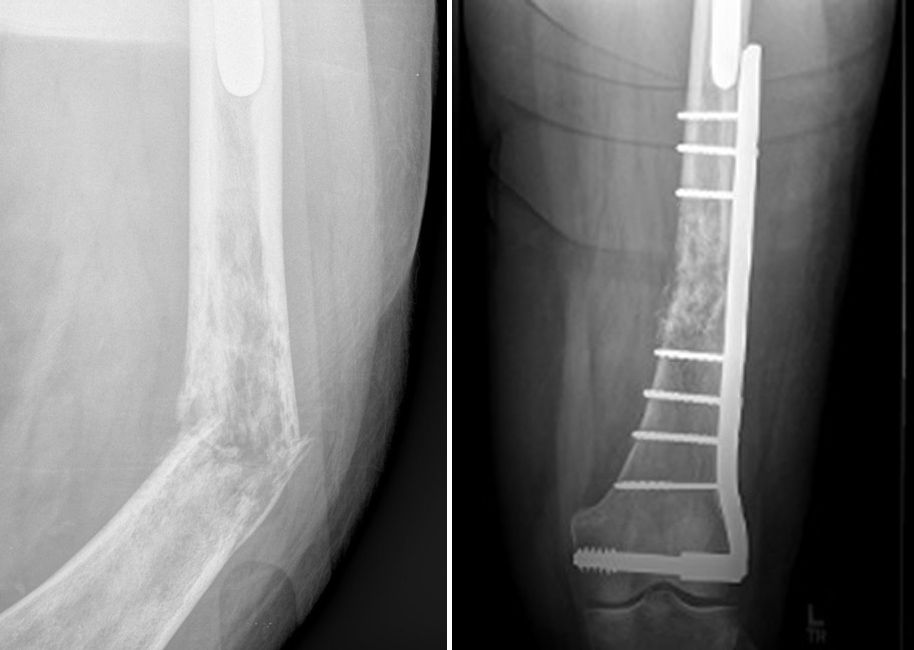

From www.researchgate.net

A 31 years female patient with bone lymphoma of left... Download Collar Bone Lump Lymphoma In rare cases, it may also be due to a. Usually, these lumps are benign (non. Enlarged lymph nodes close to the surface of the body (such as on the sides. You may get painless swellings in your neck, collarbone, armpit, groin or other parts of your body. These are swollen lymph nodes (glands). A common lymphoma symptom is lumps.. Collar Bone Lump Lymphoma.